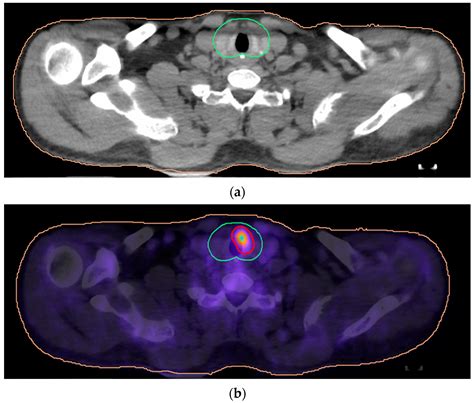

A PET/CT scan—specifically, a Positron Emission Tomography combined with a Computed Tomography scan—is a hybrid imaging technique. While the CT component provides that detailed structural map, the PET scan adds a crucial layer: metabolic function. Before a PET scan, you are injected with a radiotracer, usually a radioactive form of glucose (sugar). Cells in your body that are highly active—such as rapidly dividing cancer cells or inflamed tissues—consume this sugar at a much faster rate than normal cells.

When the PET scanner detects this higher uptake of the tracer, it creates a "hot spot" on the image. By combining the PET (metabolic) and CT (structural) data into one single, fused image, doctors can see not only where a mass is located but also how active it is biologically. This makes PET/CT scans invaluable in:

• Diagnostic clarity: Distinguishing between scar tissue (non-metabolically active) and active tumor tissue (highly active).

Conversely, if a patient has been treated for lymphoma and the doctor wants to ensure that the lingering shadow on a chest X-ray is just residual scar tissue rather than active, recurring cancer, a PET/CT is essential. A standard CT scan might show that the mass is still there, but it cannot tell if that mass is alive or dead. The PET component provides the functional insight needed to make an informed decision about the next phase of treatment.